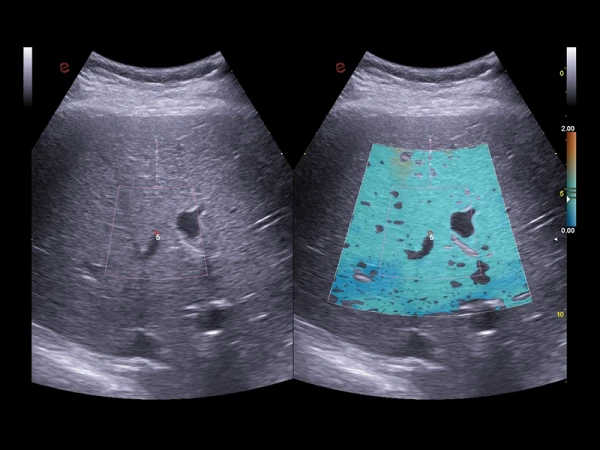

ULTRA-Color Doppler rangli xaritalash usullari: yuqori sezuvchanlik, chuqur kirish va yuqori aniqlik